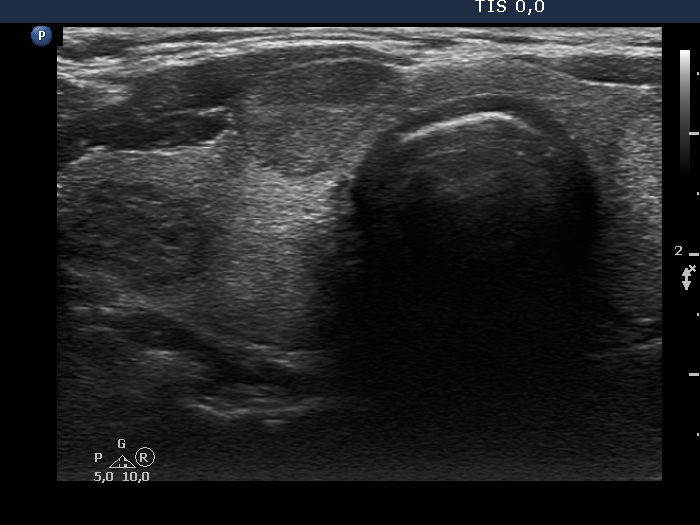

Study on 100 consecutive patients with thyroid nodule - case 009 (ultrasonographic picture 5)

Right side of the isthmus, transverse scan. The moderately hypoechoic nodule in the isthmus has halo.